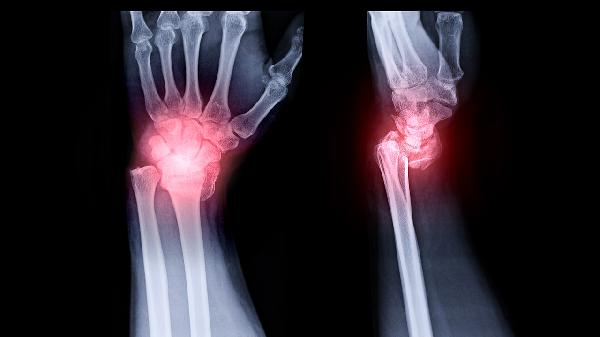

3、关节损伤:关节损伤或手术可能为结核分枝杆菌提供侵入途径,导致结核性关节炎。患者可能出现关节红肿、疼痛、活动受限等症状。治疗需结合抗结核药物和关节保护措施,如关节制动、物理治疗等,以促进关节功能恢复。